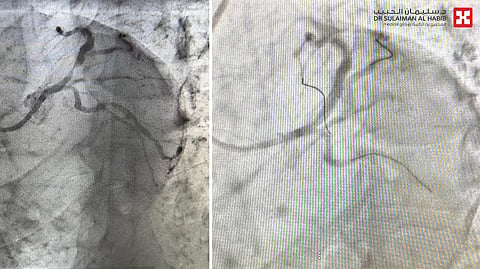

وقال د. الحربي أن المراجع أسعف إلى قسم الطوارئ، خلال وقت قصير من شعوره بالاختناق وعدم القدرة على التنفس، وكذلك آلام حادة بمنطقة الصدر، إضافة إلى أنه مصاب بأمراض مزمنة "ضغط الدم والسكري"، وأظهرت الفحوصات إصابته بجلطة حادة في الشريان التاجي الأيسر، وبعد تشخيص الحالة تم إدخاله مباشرة إلى غرفة الإنعاش القلبي ومنحه الأدوية المسيلة للدم، ثم نُقل لمختبر القسطرة القلبية، حيث تبين أن الانسداد حاد وبنسبة "99%"، وأجريت له عملية قسطرة طارئة، تم فيها، زراعة دعامة دوائية، وتأمين مرور الدم إلى القلب بشكل طبيعي، وكل ذلك تم في وقت وجيز من لحظة صوله إلى مركز الطوارئ، ثم نُقل إلى العناية المركزة للمراقبة، قبل أن يغادر إلى منزله بحالة صحية جيدة بعد أقل من "48" ساعة.

وأضاف د. الحربي الحاصل على البورد الأمريكي أن مثل هذه الانسدادات تعتبر مهددة للحياة، مشيراً إلى أن نجاح التدخل الطبي العاجل يعتبر امتداداً للنجاحات الطبية للمستشفى، مبيناً أن كفاءة الفريق الطبي والتجهيزات الطبية المتقدمة سواء العلاجية أو التشخيصية ساهمت في نجاح العملية.